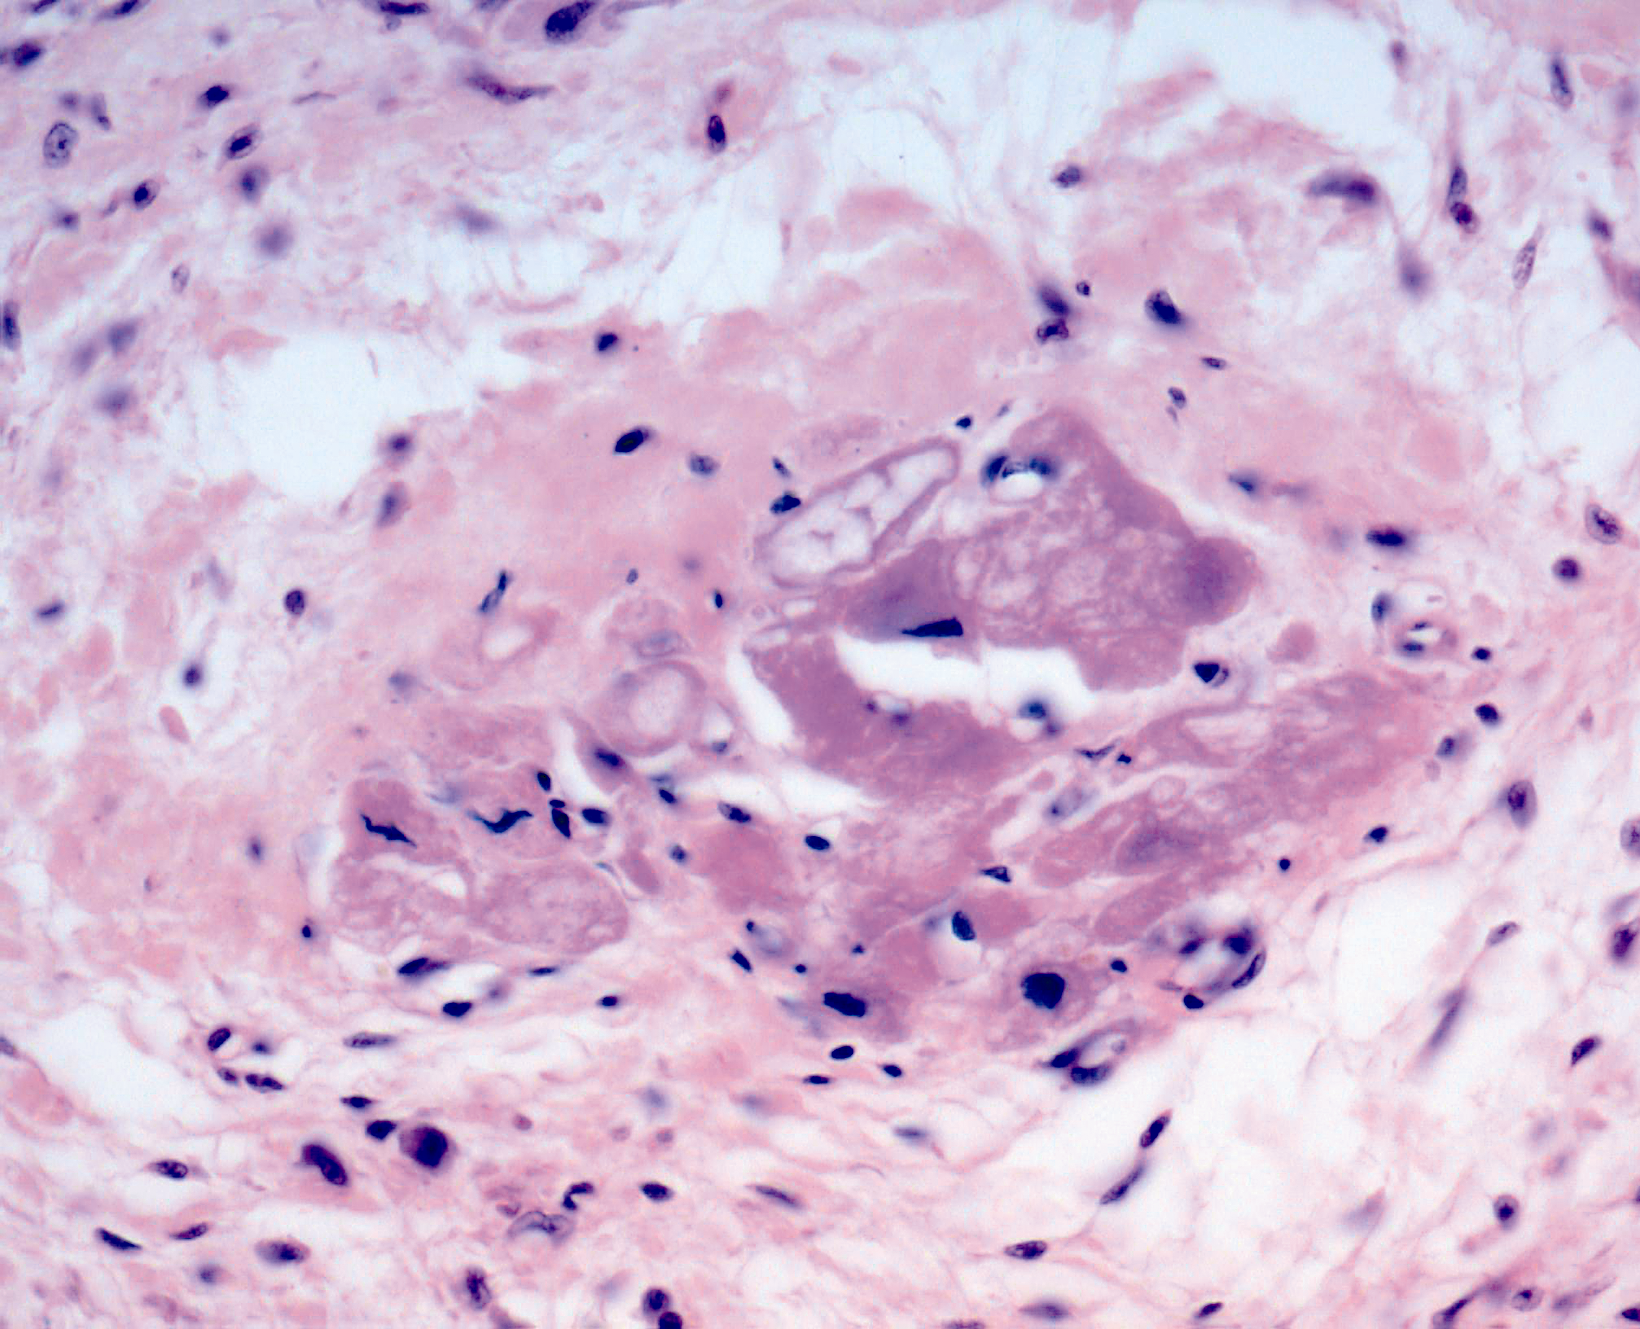

Межуточный миокардит: гистологические исследования

Раздел: Идеи и советы